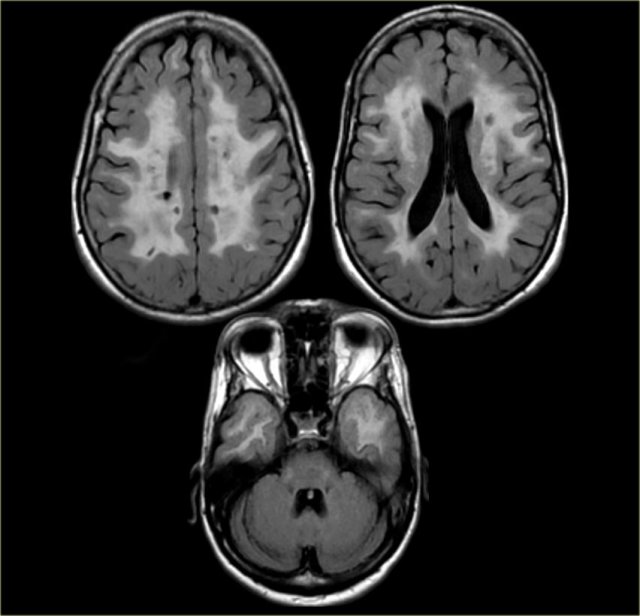

On the left we see a patient who was diagnosed as having VaD.

White matter disease is seen as severe WMH (hypointense on T1) in the periventricular regions.

In addition to these vascular changes, there is also MTA.

Presumably this patient has both VaD and AD, a finding seen in many elderly patients.

These findings should be described separately as it may have therapeutic consequences.